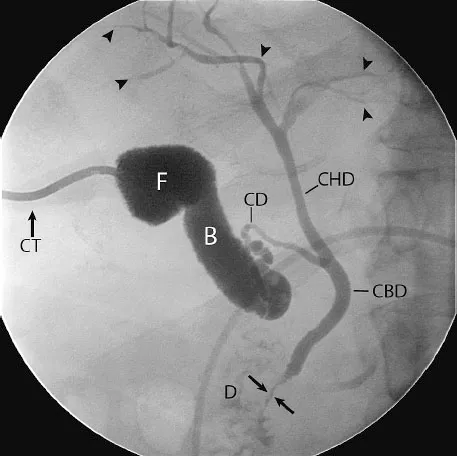

- Intrahepatic Ducts: Right & Left hepatic ducts converge to form Common Hepatic Duct (CHD).

- Extrahepatic Ducts:

- Gallbladder → Cystic Duct.

- Cystic Duct + CHD → Common Bile Duct (CBD).

- CBD + Pancreatic Duct → Ampulla of Vater → Duodenum.